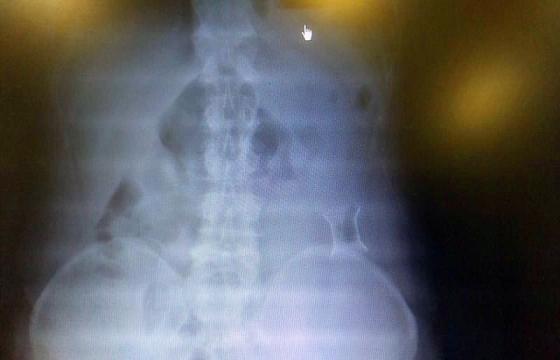

受試患者在結(jié)腸端端吻合術(shù)中,使用我司新研制產(chǎn)品達到了理想的預(yù)期效果?;颊咝g(shù)后7天、14天X光片顯影,可降解腸道支架均能按研制設(shè)計的預(yù)期時間節(jié)點保持應(yīng)有強度,術(shù)后21天X光片顯示可降解腸道支架已完全破碎,并排出體外。在整個試驗過程中,病患無任何不良反映,耐受良好。